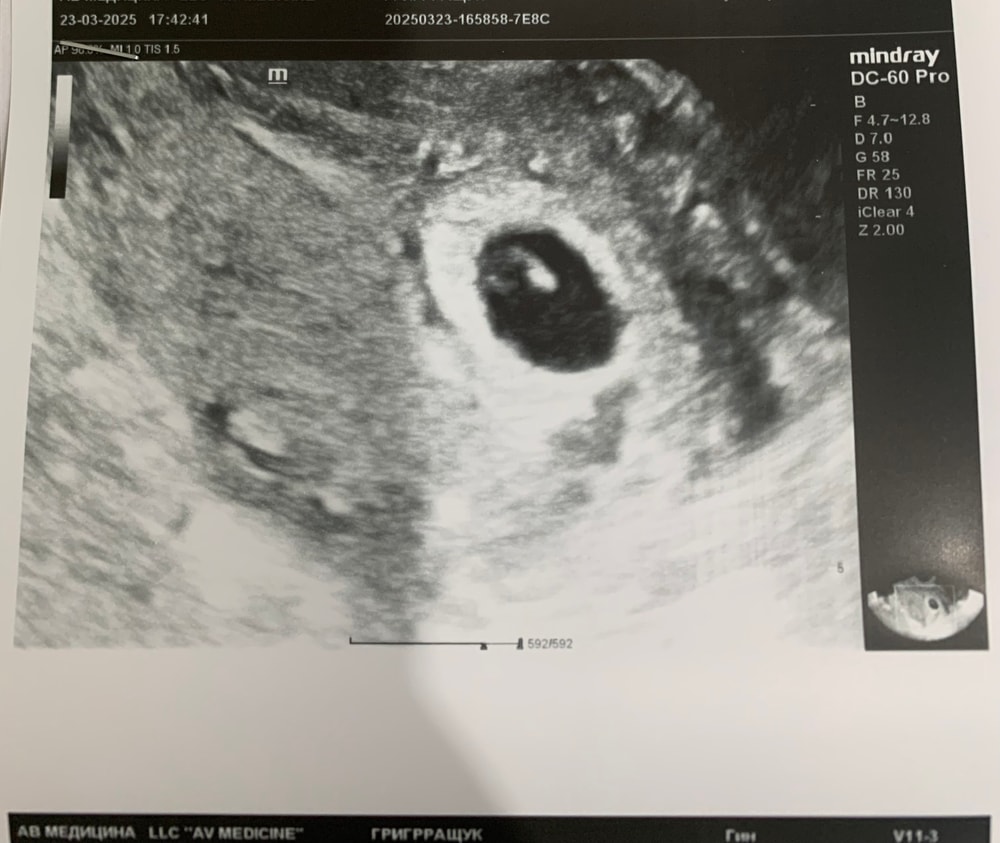

24 дпп ровно 6недель

Была на узи, сб+ ктр 3мм, малыш в матке☺️